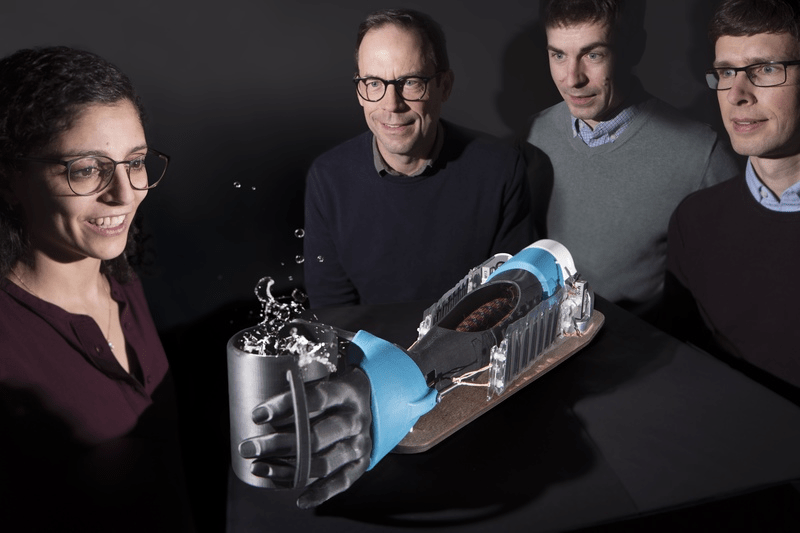

Artificial muscles for tremor suppression

Read more: Artificial muscles for tremor suppressionSource:Max Planck Institute for Intelligent Systems FULL STORY It is estimated that around 80 million people worldwide live with a tremor. For example, those who live with Parkinson’s disease. The involuntary periodic movements sometimes strongly affect how patients are able to perform daily activities, such as drinking from a glass or writing. Wearable soft robotic…